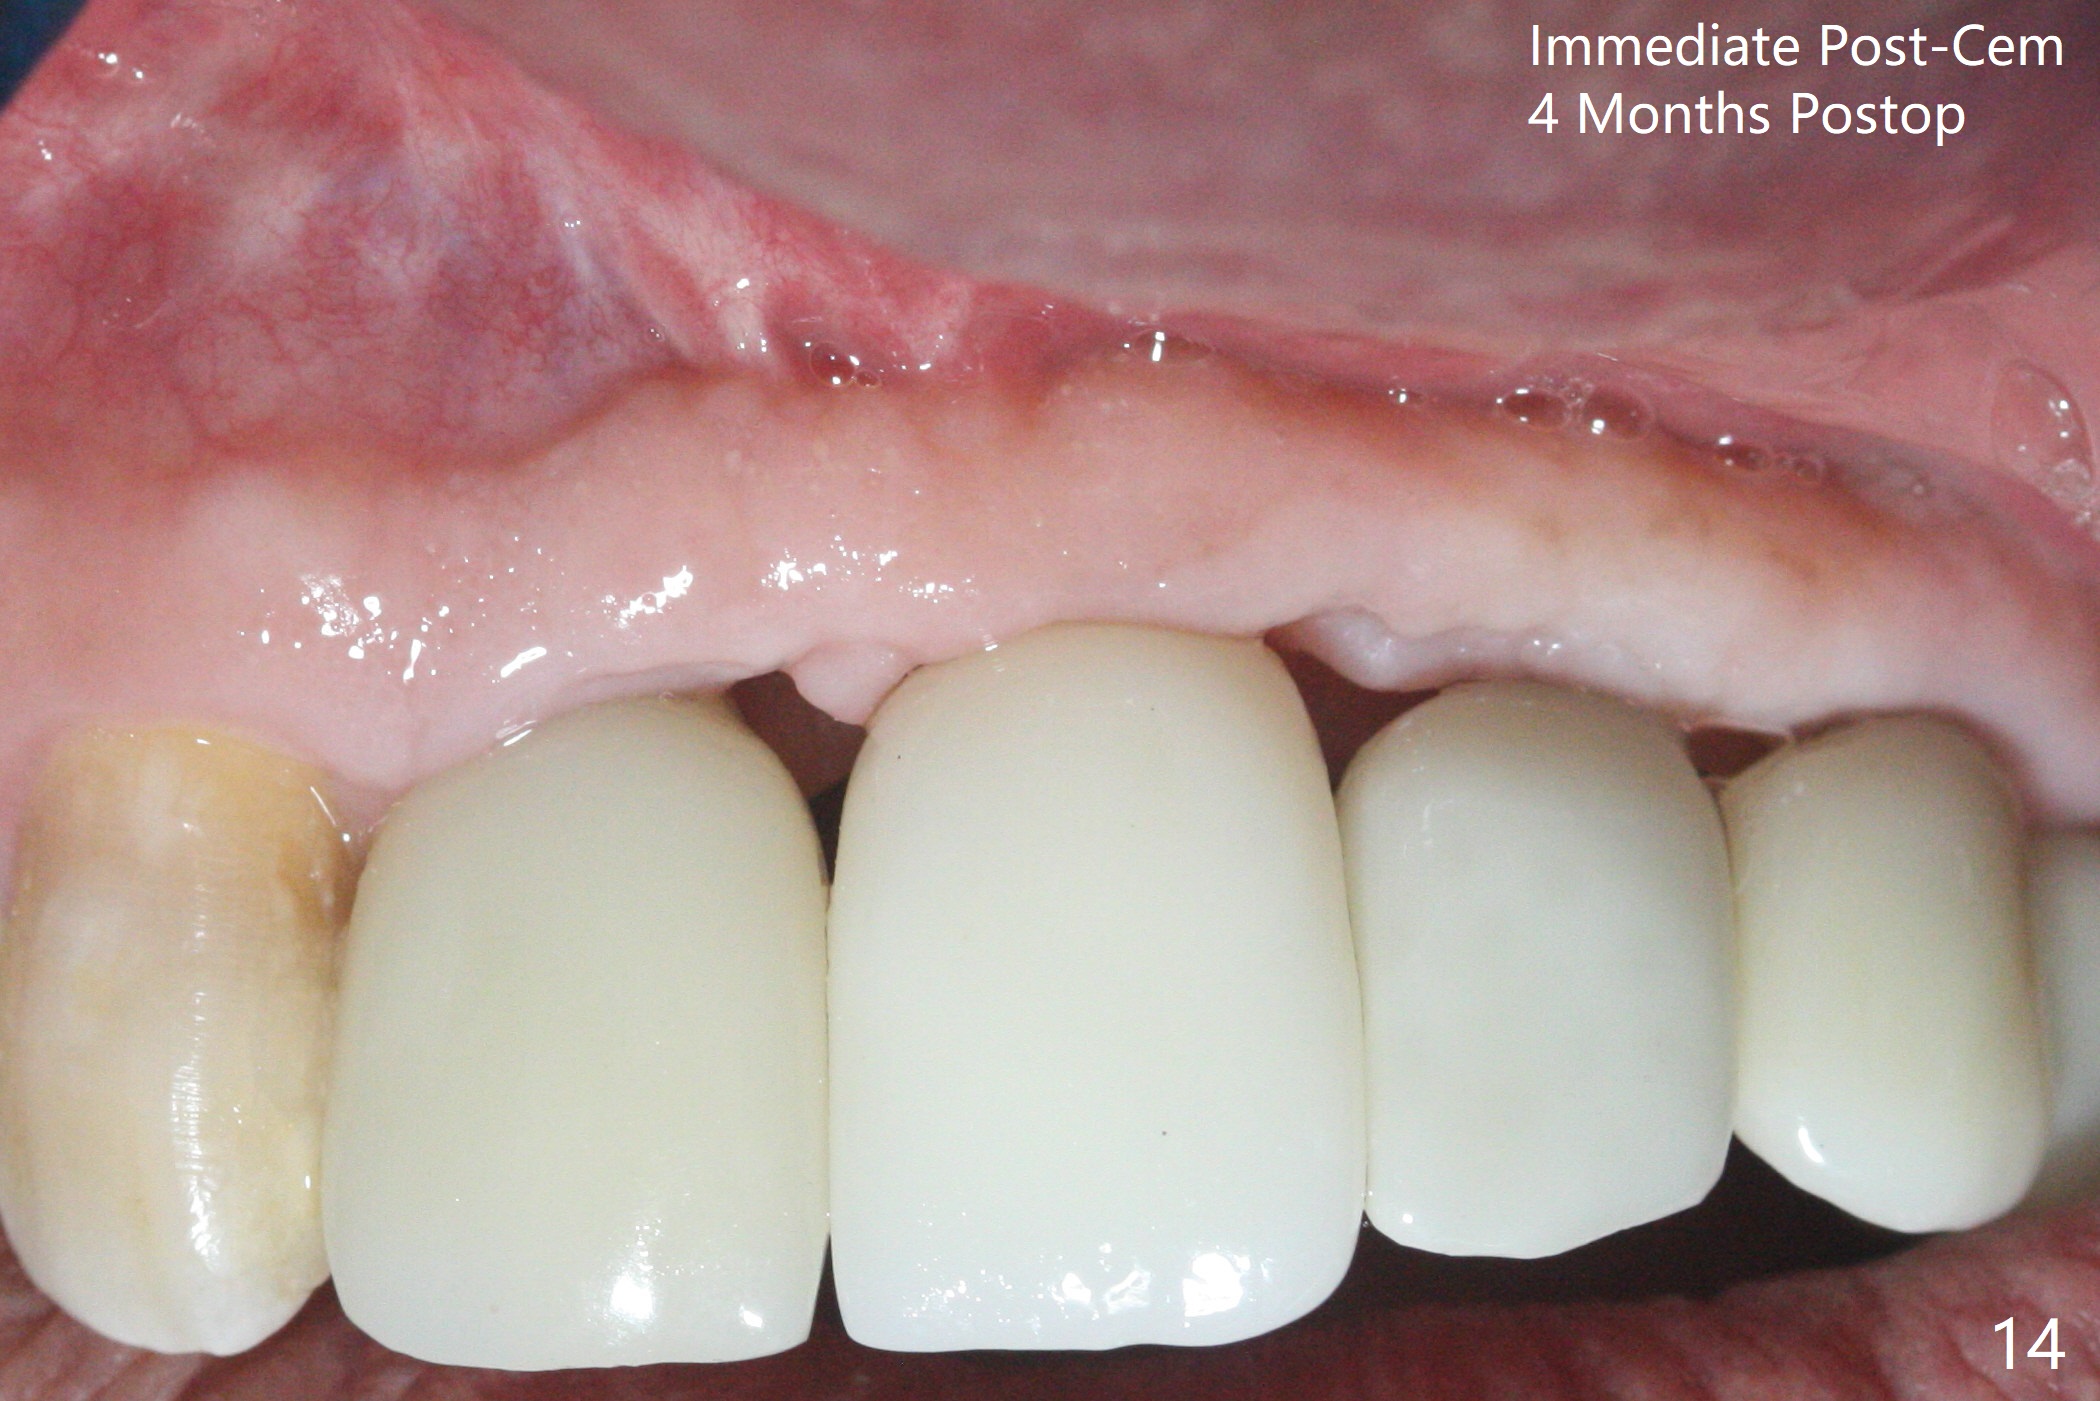

The implant access at #9 closes 1 week post implant fracture (Fig.1,4). There is mild gingival erythema at #10 (Fig.2,3 ^). There is bone around the fractured implant, which is palatally placed (Fig.5). The 2 mm implant is removed using 2/3 mm trephine bur. In spite of moving the osteotomy buccally, a 4.5x4 mm, 15 degree A-type angled abutment is installed for an immediate provisional following placement of a 3.5x10 mm implant (Fig.7, 25 Ncm). Sticky bone is placed (Fig.7 *) palatal to the implants at #9 and 10 (with thread exposure, Fig.6). While the majority of periodontal dressing remains in place (Fig.9,10), the suture in the exposed area appears to hold the papilla in place (Fig.8 <). Herpetic infection develops in the palate (Fig.9). Two months later, the gingiva at #10 is healthy; it appears that the implant threads are covered by bone graft. The immediate provisional (fabricated before suture) keeps the gingiva in an ideal position for impression of final restoration. It appears that the access hole is in a right area for screw retained restoration. The gingival cuff is healthy immediate pre-cementation, 4 months postop (Fig.12,13). The lab does not make access hole for the final crown (Fig.14). The implant remains subcrestal 4 months postop (Fig.15). Since the shade of the crown is off, the abutment remains un-torqued and the crown is cemented with temp bond. The implant threads at #10 seem to be covered by bone graft 4 months postop (Fig.16).